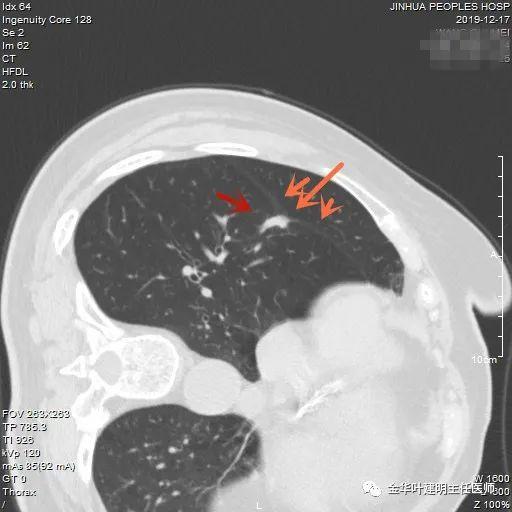

上图示结核。我们发现其有明显的卫星灶,如绿色箭头所示,主病灶处也是周边有模糊区域,病灶整体密度较为均匀(肿瘤容易生长不均致密度欠均匀,显杂乱)。